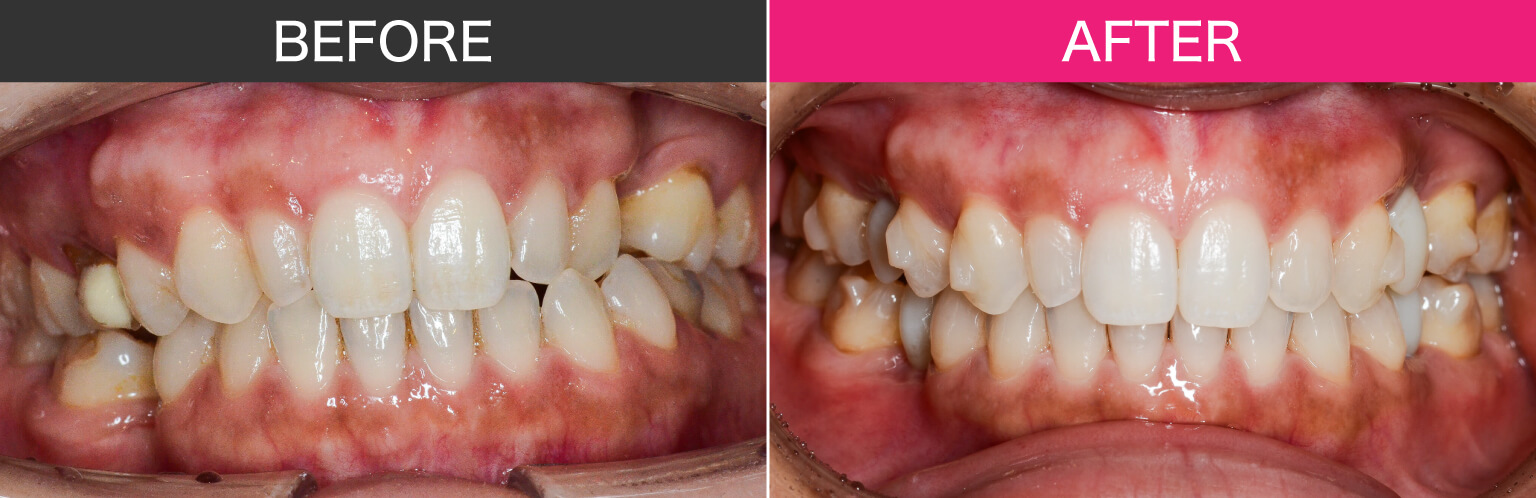

矯正開始から2年半経過

11.術前術後正面

12.術前術後右

13.術前術後左

インプラントを埋入した後は、インプラントがしっかり結合(オッセオインテグレーション)するまでの待機期間が必要になります。

この期間も治療を止めるわけではなく、患者さまにはマウスピース(インビザライン)を引き続き使用していただき、矯正治療を継続しています。

現在、矯正治療開始から約2年半が経過しており、インプラント部分にはプロビジョナル(仮歯)を装着し、矯正治療で歯並びの細かい微調整を進めています。

矯正治療が完了した段階で、インプラントには最終補綴物としてジルコニアの上部構造を装着し、治療が完了する予定です。